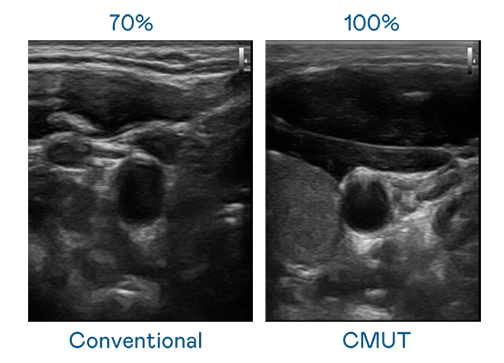

CMUT 技术是一种用电容式微机电元件来产生超音波讯号的技术。与传统 PZT 压电式技术相比,CMUT 频宽增加 30%,更宽频的超音波讯号让影像解析度大幅提升,是实现高影像品质医疗超音波扫描、促进精准医疗发展的关键技术。

大频宽带来超清晰影像

超音波影像的解析度高低,首先取决于探头能发出的讯号频宽。j9九游会首页登录 CMUT 可提供高清晰的超音波讯号,提供高频宽、高灵敏度、影像纹理细节更高的超音波影像,协助医护人员缩短影像判读时间及利用精准的医疗影像进行诊断。